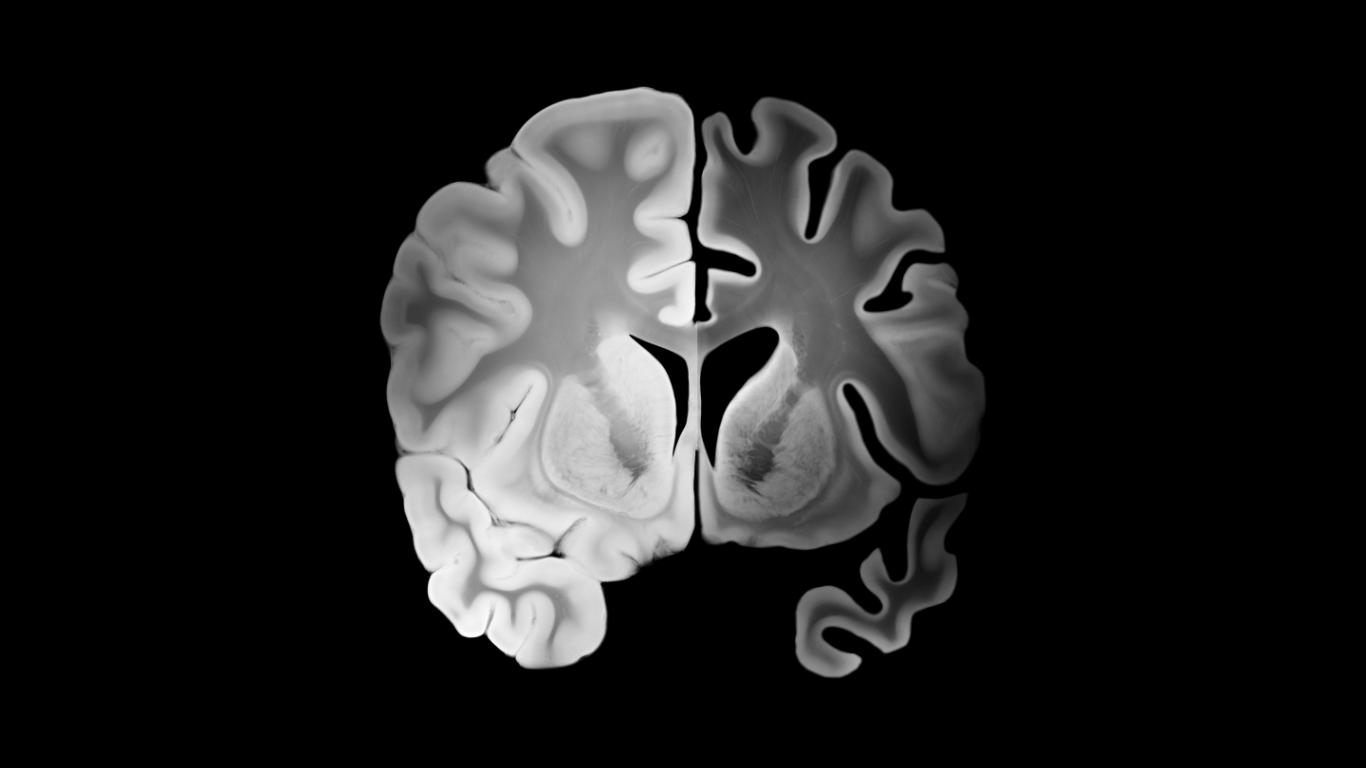

El Alzheimer es el gran misterio de la pérdida de memoria mayormente en adultos mayores, y hasta ahora, solo podemos intentar frenarlo. Pero la buena noticia es que un estudio publicado en Ageing research reviews en el 2024, los investigadores han descubierto una pista enorme: el Alzheimer y la Diabetes Tipo 3 (problemas con el azúcar en la sangre) son como primos hermanos que aparecen juntos, especialmente con la edad. La ciencia nos dice que esta conexión no es casualidad; el cerebro de las personas con Alzheimer empieza a tener problemas para usar el azúcar, casi como si se volviera “resistente a la insulina”, al igual que en la diabetes.

El cerebro, a pesar de ser solo el 2% del peso corporal, consume aproximadamente el 20% de la glucosa del cuerpo. La insulina es vital no solo para ayudar a las células a absorber la glucosa, sino también para la memoria y la función cognitiva. Imagina lo siguiente: Tu cerebro funciona con glucosa (azúcar) como si fuera gasolina, y la **insulina** es la llave que abre la puerta de las neuronas para que esa gasolina pueda entrar. En el Alzheimer, esa llave deja de funcionar bien; las neuronas se vuelven “sordas” a la insulina.

¿Qué pasa entonces? El cerebro se queda sin su energía principal (un estado de “hambre”), lo que lo debilita. Además, cuando la llave no funciona, se interrumpe la capacidad de la insulina para enviar mensajes de **crecimiento y reparación** a las neuronas. Esta doble falla no solo agota la energía, sino que también crea un ambiente tóxico que promueve la **inflamación** y la acumulación de las proteínas pegajosas (las placas beta-amiloide y los ovillos de Tau) que terminan dañando la comunicación entre las células cerebrales. En resumen, tu cerebro, esa supercomputadora, se queda sin energía y sin protección, pero el origen es algo que podemos influir: ¡su capacidad para manejar el azúcar!